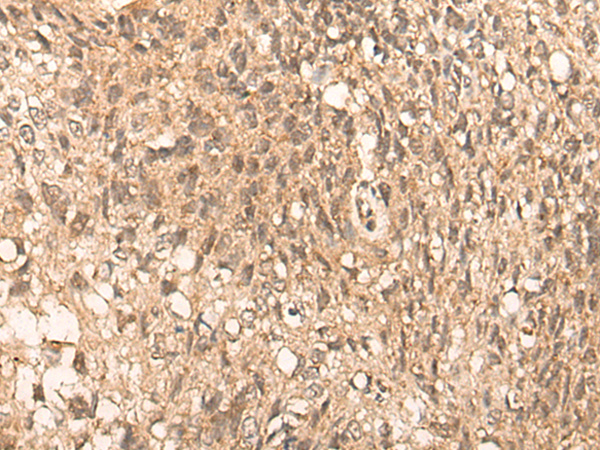

The image is immunohistochemistry of paraffin-embedded Human lung cancer tissue using P04663(PFKFB4 Antibody) at dilution 1/35. (Original magnification: ×200) |